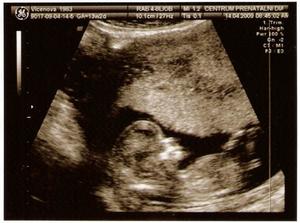

Na NT screeningu to bylo super, viděli jsme krásný mimísko! Všechno je v pořádku, i testy z krve. Měříme 10,1 cm a podle slov pana Dr. máme velkej a kvalitní nosík 🙂 Zatím vypadáme na holčičku, tak uvidíme, jestli se nám to později potvrdí nebo tam máme stydlínka 🙂 Termín porodu zůstává stejně jako podle MS - 18.10.2009.